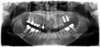

3 implants coniques en bas à droite, parallèles entre eux, et parallèles à l’axe des dents voisines, avec leur vis de cicatrisation, remplaçant les racines des 2 premières molaires

3 implants coniques en bas à gauche, parallèles entre eux, et parallèles à l’axe des dents voisines, avec leur vis de cicatrisation, remplaçant les racines des 2 premières molaires